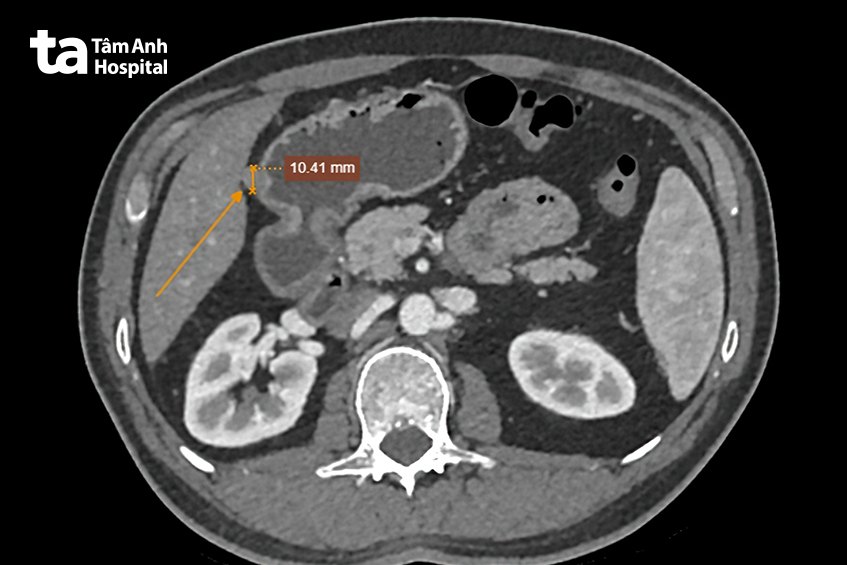

Kết quả chụp cắt lớp vi tính (CT) bụng còn cho biểu hiện dày thành dạ dày lan tỏa, mất cấu trúc lớp dạ dày, thâm nhiễm mỡ xung quanh. Sinh thiết ghi nhận ung thư biểu mô tuyến kém biệt hóa (bệnh lý ác tính). “Nếu chị Huê khám phát hiện bệnh sớm hơn ngay từ khi có triệu chứng, cơ hội điều trị sẽ cao hơn”, bác sĩ Hùng cho biết.